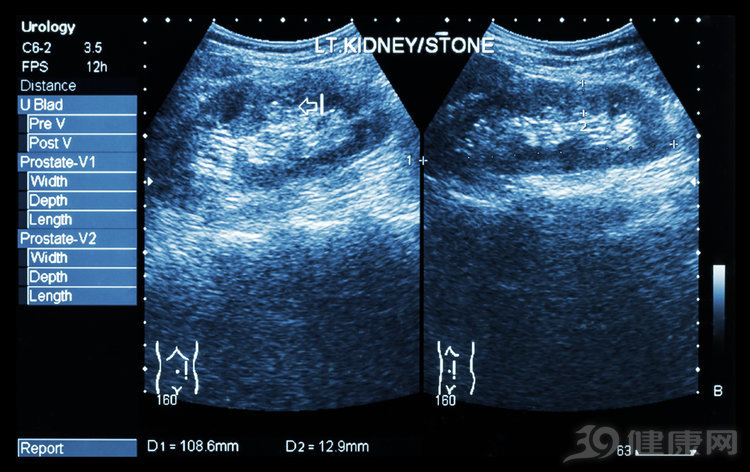

丽霞在高二寄宿的时候,由于学校水质问题,得了右肾结石,并伴随出现积水。

在医院做完体外碎石,安稳度过3年之后,当丽霞认为自己已平安度过“难关”的时候,肾结石又再一次地来了,而且更为猛烈。

此外,能够引起疼痛的结石都是比较小的结石,因为只有小结石才会移动,不会疼的大结石,才是真正的“隐形杀手”,它会使肾脏功能慢慢损伤,直到不可控制的地步。

当结石堵塞了输尿管或是肾盂时,也会造成尿液排出不畅,引起肾积水。

一般来说,小于1cm的结石属于小结石,而且,如果这种小结石又比较“安分”,不会给身体带来影响,或者造成疼痛、感染等问题,是不需要治疗的,因为这种小结石可能会自行排出体外。

大于1cm的结石,或者是出现感染、疼痛等症状的结石,则需要尽快到医院做手术。目前来说,对肾结石的手术治疗主要有四种,分别是肾盂或肾窦切开取石术、肾实质切开取石术、肾部分切除术以及肾切除术。